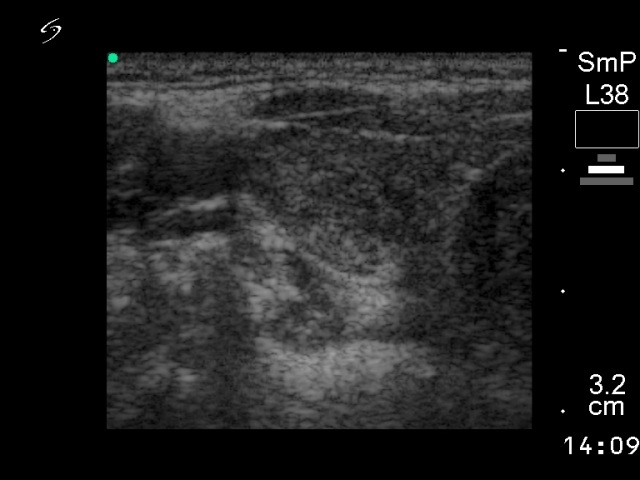

Ultrasonography: the thyroid was echonormal with small hypoechogenic foci. An echonormal nodule with a halo sign in the left lobe.